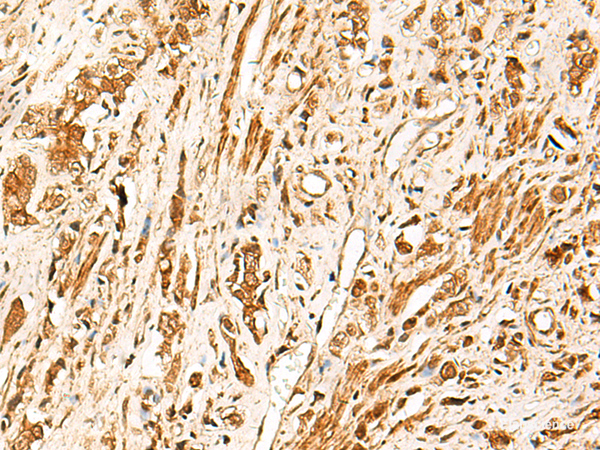

This gene encodes a member of the T-cell factor/lymphoid enhancer-binding factor family of high mobility group (HMG) box transcriptional activators. This gene is expressed predominantly in T-cells and plays a critical role in natural killer cell and innate lymphoid cell development. The encoded protein forms a complex with beta-catenin and activates transcription through a Wnt/beta-catenin signaling pathway. Mice with a knockout of this gene are viable and fertile, but display a block in T-lymphocyte differentiation. Alternative splicing results in multiple transcript variants. Naturally-occurring isoforms lacking the N-terminal beta-catenin interaction domain may act as dominant negative regulators of Wnt signaling. Protein function: Transcriptional activator involved in T-cell lymphocyte differentiation. Necessary for the survival of CD4(+) CD8(+) immature thymocytes. Isoforms lacking the N-terminal CTNNB1 binding domain cannot fulfill this role. Binds to the T-lymphocyte-specific enhancer element (5'-WWCAAAG-3') found in the promoter of the CD3E gene. May also act as feedback transcriptional repressor of CTNNB1 and TCF7L2 target genes. TLE1, TLE2, TLE3 and TLE4 repress transactivation mediated by TCF7 and CTNNB1. [The UniProt Consortium]